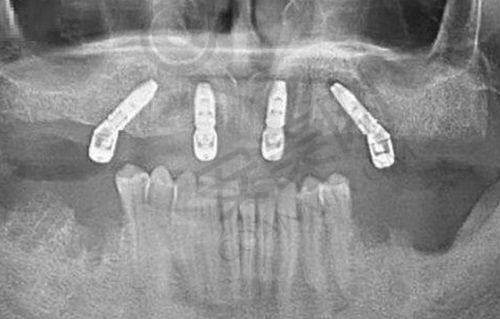

三亚舒诺口腔医院开展的诊疗项目涵盖了口腔的多个领域。种植牙方面,从单颗到全口种植都能提供服务,并且提供多种品牌的种植体,满足不同患者的需求。比如对于单颗牙齿缺失的患者,可以选择合适的种植体进行修复;而对于全口牙齿缺失的患者,医院也有专精的方案来解决问题。牙齿矫正包括隐形矫正、金属托槽矫正等,能满足不同年龄段患者的需求。隐形矫正美观舒适,适合对美观要求较高的患者;金属托槽矫正则价格相对较为亲民,矫正成效也十分显著。牙齿美白采用精良的美白技术,让您的笑容更加迷人。通过专精的美白方法,可以有效去除牙齿表面的色斑和污渍,使牙齿变得更加洁白亮丽。儿童齿科专为儿童设计了口腔保健服务,确保孩子们在愉悦的环境中接受治疗。医院会采用一些有趣的方式来吸引孩子的注意力,减轻他们对看牙的恐惧。牙周治疗针对牙周疾病提供专精的治疗方案,帮助患者解决牙龈出血、牙周炎等问题。

三亚舒诺口腔医院聚集了一支经验多的医生团队,他们在各自的专精领域都有独特的见解和技术。张颖医生在口腔种植领域拥有多年临床经验,擅长单颗、多颗牙种植及全口种植修复。她对复杂的种植实例,如骨量不足的患者,具有独到的处理方法,手术操作细腻,注重患者的舒适度和术后成效。在为骨量不足的患者进行种植手术时,她能够采用精良的技术和方法,增加种植的成功几率。王晓娜医生专注于牙齿矫正,有着丰富的临床经验。她能够根据患者的具体情况制定个性化的矫正方案,尤其在隐形矫正和成人复杂正畸方面,深受患者信赖。对于一些牙齿排列不整齐、咬合关系紊乱的患者,她能够精细地制定矫正计划,帮助患者修复正常的牙齿功能和美观。张泽奇医生则在补牙、拔智齿和假牙修复等项目上表现出色。他的技术娴熟,能够有效降低患者的疼痛感,实现良好的治疗成效。在拔智齿时,他能够熟练地操作,减少手术创伤,让患者在术后更快地修复。

三亚舒诺口腔医院的收费透明合理。进口DIO亲水型植体1580元起/颗,韩国登腾植体1980元起/颗,金属自锁矫正6999元起,隐适美隐形矫正24800元起,爱尔创牙冠880元起/颗,拔智齿150元起/颗。需要注意的是,以上价格仅供参考,实际价格可能会有所浮动。在治疗前,医院会详细告知患者费用明细,确保没有隐形消费。患者可以根据自己的经济情况和口腔状况,选择适合自己的治疗方案和材料。